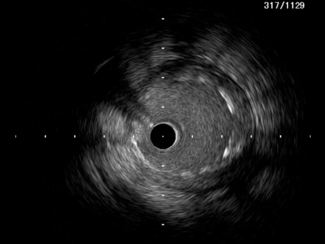

Sriram Veeraraghavan, MD, DM; Bharath Raj Kidambi, MD, DM

A 73-year-old woman with diabetes, hypertension, and non-ST elevation myocardial infarction underwent optical coherence tomography-guided angioplasty for calcific stenosis of the mid-left anterior descending artery and mid-segment of a...